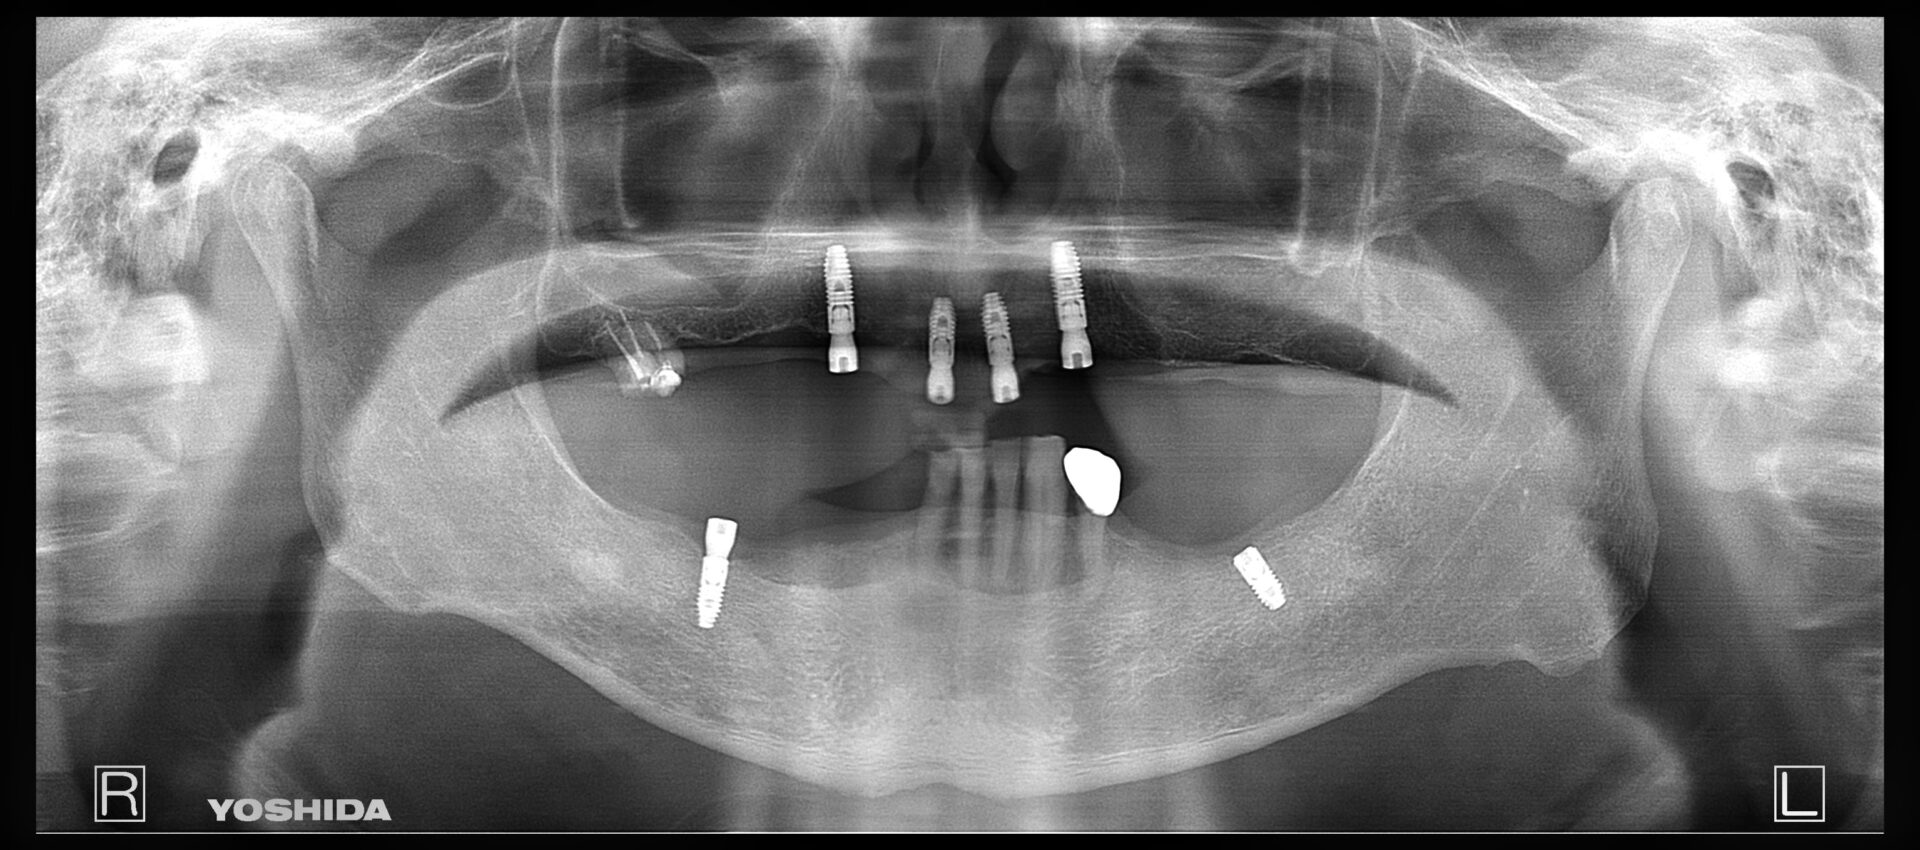

Case

50代 女性

左下の6番目の歯を失われ、その後の治療のご相談に当院にお見えになりました。

インプラント治療は少し恐怖心があるとのことや、隣の歯を削ることにも抵抗があり入れ歯の針金にも抵抗があるとのことで今回はノンクラスプデンチャーという見た目のよい入れ歯を選択頂きました。型取りも含めて2回で治療は終了です。

見た目もよくなんでも噛めるとのことでご満足いただいております。また、少し見える金属の部分に関してはここが非常に重要で、この部分がないと入れ歯は沈み込んでしまい痛みなどがでてしまいます。そのため、沈み込み防止の為にこの部分は必須になります。ここがあるおかげでしっかりと安定しよく噛める入れ歯が完成します。

治療部位 | 左下6 |

費用 | 150000円 |

治療期間 | 1か月 |

注意事項(リスク・副作用など) | 入れ歯を固定する天然歯に負担がかかることがあります。 |

カテゴリ | 入れ歯 |